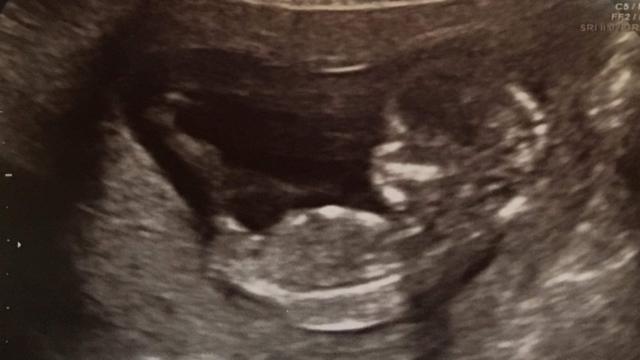

caça nick Uma mulher que sofreu 13 abortos espontâneos deu à luz uma menina após ser submetida a um tratamento pioneirocaça nickfertilidade caça nick .

Onze gestaçõescaça nickLaura Worsley,caça nick35 anos, terminaram no primeiro trimestre, mas ela também perdeu dois meninos quando estava na 17ª e 20ª semanacaça nickgravidez.

Laura e o marido Dave,caça nickKenilworth, na Inglaterra, tentaram pela 14ª vez e, com a ajudacaça nickQuenby ecaça nickequipe, tiveram uma filha chamada Ivy.